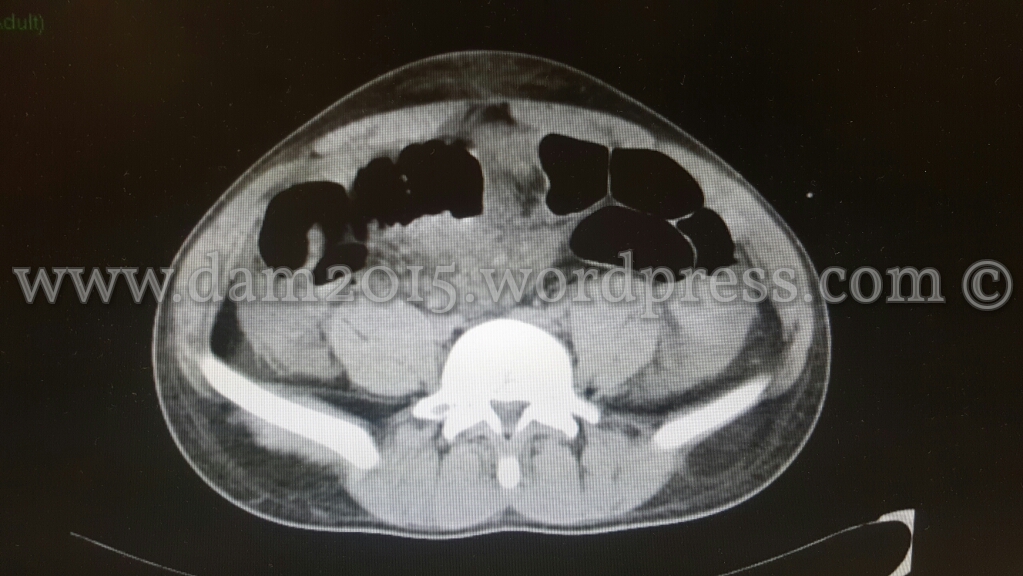

Eseguita nuova TC addome che mostrava incremento dell’imbibizione edematosa-emorragica del tessuto adiposo sottocutaneo e comparsa di marcato ispessimento edematoso delle anse del piccolo intestino ove sembrava apprezzarsi discontinuità della parete intestinale; presenza di bolle di aria libera come per perforazione di viscere cavo.